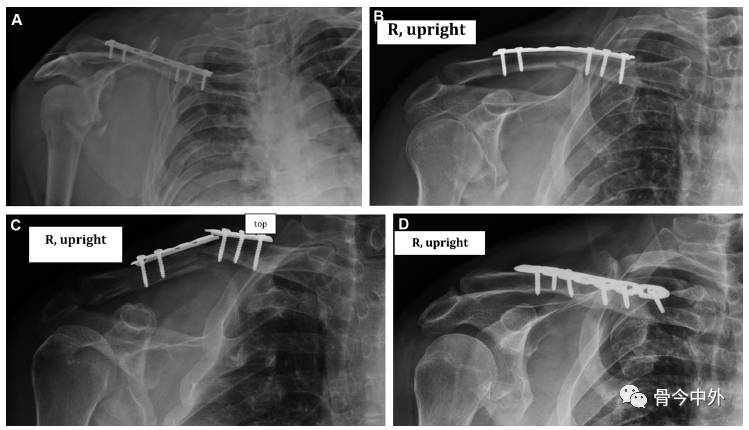

综述教程:锁骨骨折治疗的六大关键问题(下)